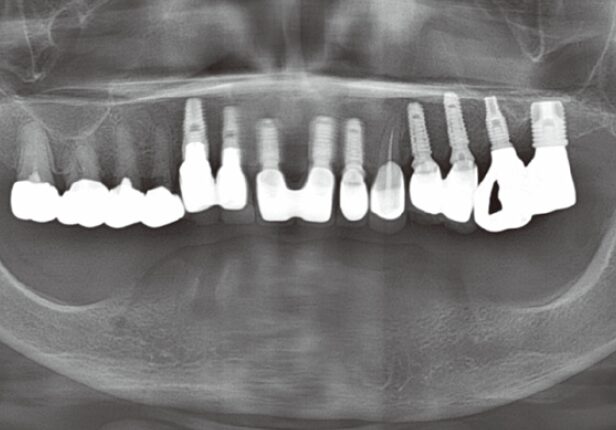

Mandibular Full case

Pre-surgery panorama